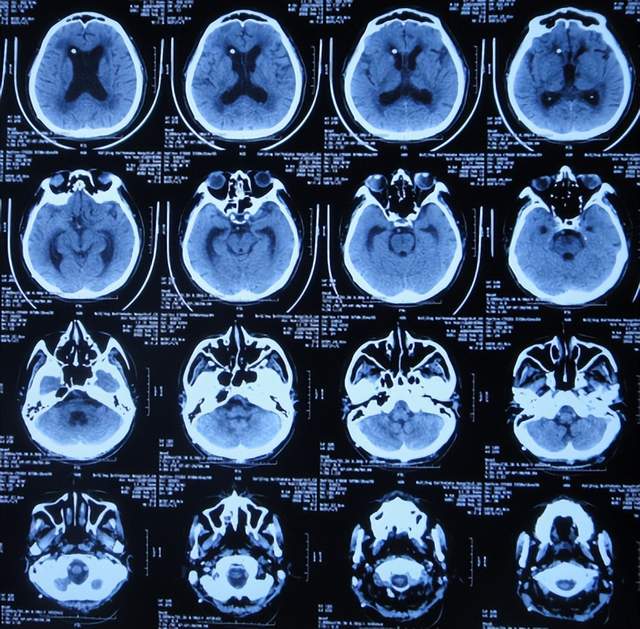

出院后4个月即2022年8月30日,为了做脑积水分流术,再次来到李小勇脑脊液科,入院时:精神状态良好,能自己走路了稍不稳(图-25);头颅CT示脑室引流术术后状态(图-26)。

图-26:2022年8月30日头颅CT

完善各项检查后于2022年9月15日,进行了脑室腹腔分流术(图-27)。

图-27:2022年9月15日头颅CT

脑室腹腔分流术后13天即2022年9月28日出院。出院时:走路进一步变稳,身体其他均正常(图-28)。